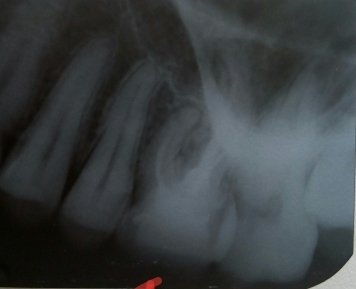

Здравствуйте. Некоторое время назад, в запломбированном ранее 46 зубе (предпоследнем внизу справа), выпала часть пломбы. В одной из клиник сказали что восстановить пломбу нельзя, из-за воспалительных процессов на корнях зубов, и необходимо удаление. Прийдя на удаление в другую, сказали что зуб можно вылечить — после перепломбировки каналов воспалительные процессы прекратятся сами собой со временем

Не могли бы вы сказать по снимку, стоит ли все же пытаться вылечить этот зуб, и не будет ли это вредным в долгосрочной перспективе. Безмерно благодарен заранее.

Добрый день, уважаемый Павел. Воспаление слишком обширное, но попытаться спасти можно. Вы должны понимать, что для полного восстановления возможно понадобится около полугода. Так же хочу отметить, что гарантий на это лечение никто вам не даст, и еще, после лечения через несколько лет также возможен рецидив. Тут вам решать, попробовать конечно можно, но и необходимо понимать всю глубину проблемы. Вам необходим очень грамотный терапевт-эндодонт а также не малые вложения. Если вы в Москве и потребуется профессиональный доктор обращайтесь, я вам помогу. Всего доброго!